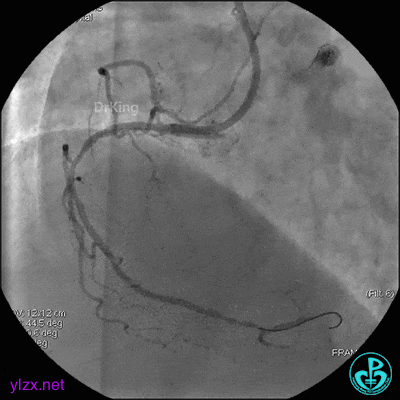

最后造影结果显示前降支3级血流,支架膨胀尚可。